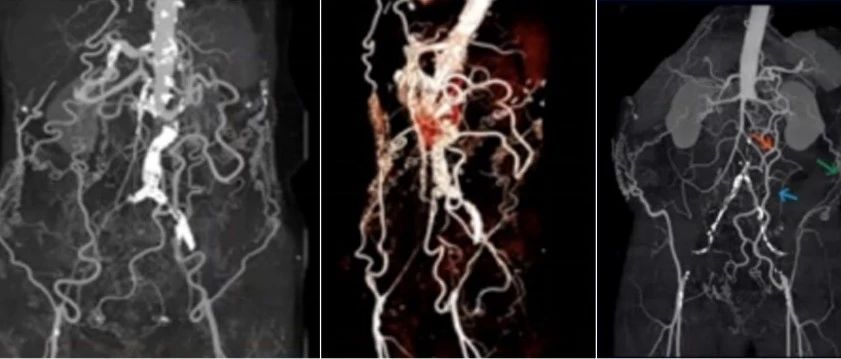

2022 CEC 手术精选 | 张宏鹏:白塞病合并多发动脉瘤的腔内治疗